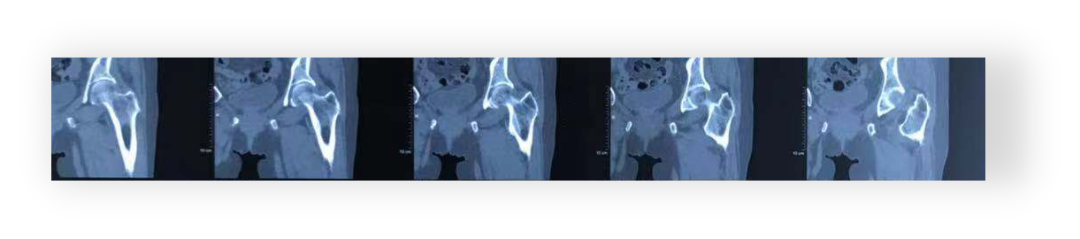

髋关节CT(2024-07-19):双侧髋关节退行性变。